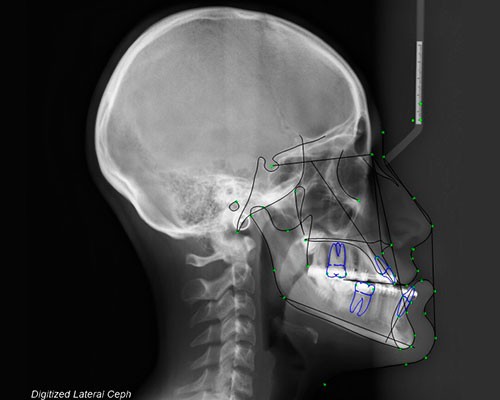

SISTEMAS DIGITALES 3D